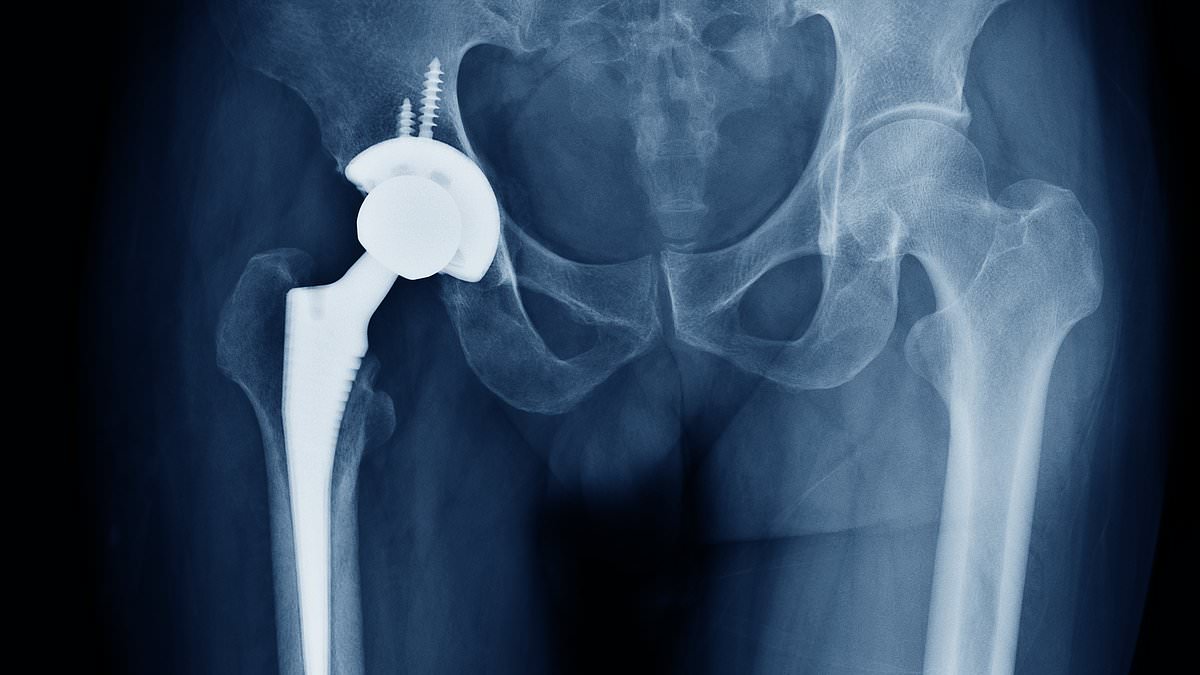

Bone cement, a seemingly simple material, plays a vital role in orthopaedic surgery. It acts like a strong grout, filling the gap between metal implants and bone to create a stable bond that keeps the joint in place. Some formulations include antibiotics, crucial for preventing infections during high-risk procedures or revision surgeries where previous implants have failed. Without this cement, surgeons may be forced to use alternative methods that are less reliable or delay operations until supplies are restored. The issue is not just about a single product—it's about the intricate web of supply chains that sustain modern healthcare.